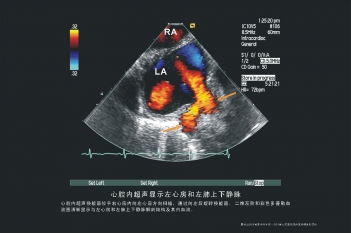

静脉图

希氏束起搏电极置放